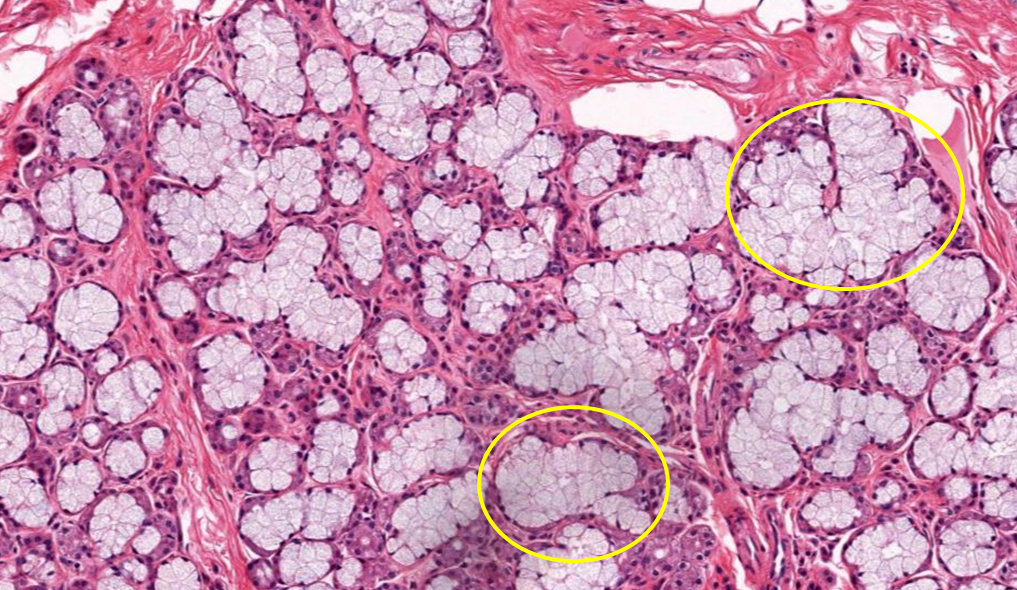

Glândula exócrina (destaque de ácinos mucinosos)